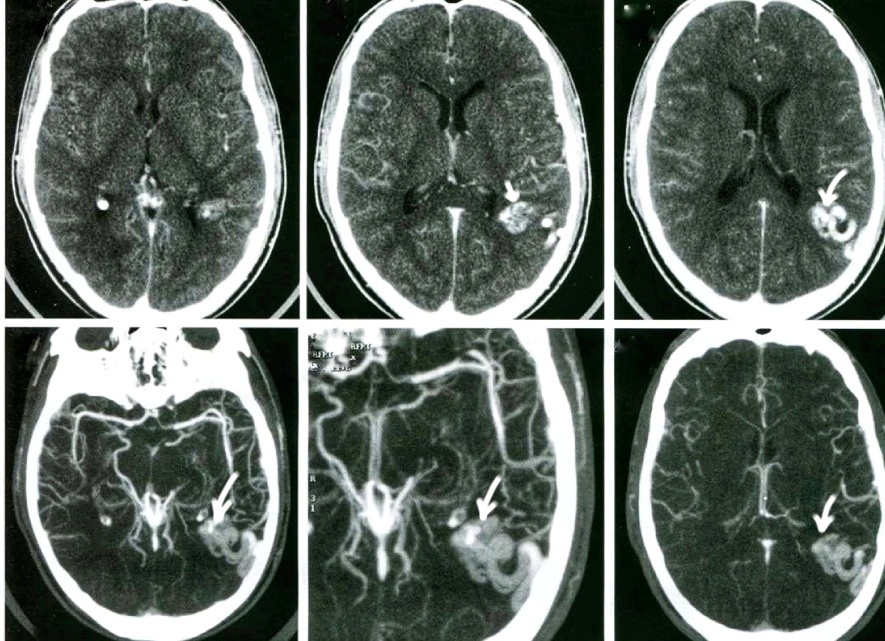

Так на МСКТ-ангиографии (МIP-реконструкция) выглядит артериовенозная мальформация (АVM) теменной области слева (указано стрелками) в виде клубка сосудов, интенсивно накапливающего контрастное вещество (кровоснабжение из конечных ветвей СМА)